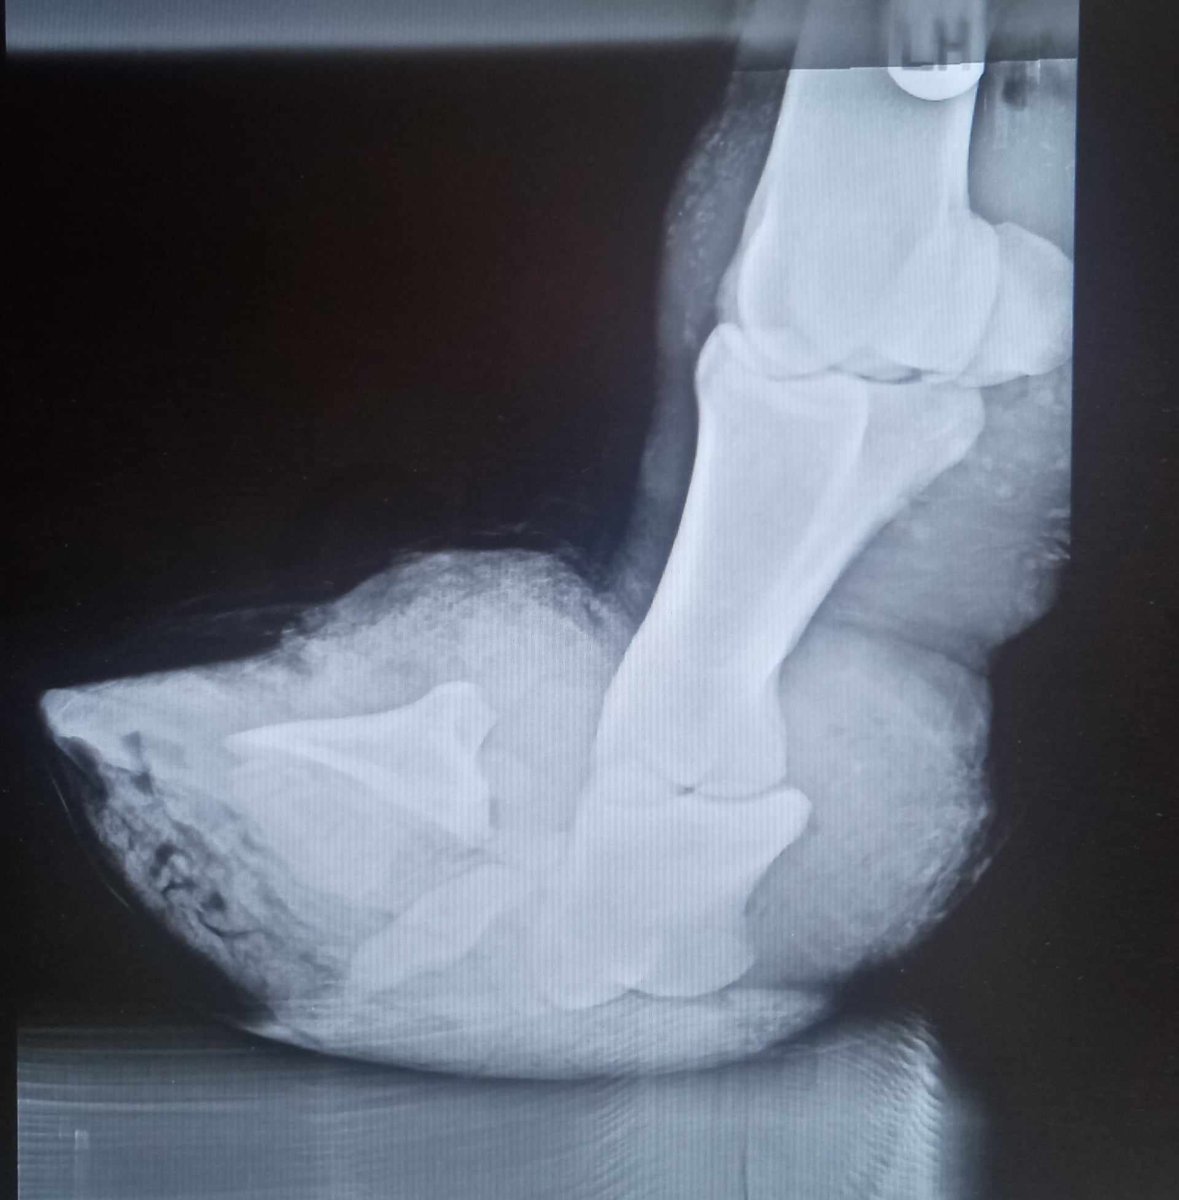

A rozložený kopytný kĺb ste už videli? ☹️

Obrázek

Dodnes jsem netušila, že něco takového může být možné -  bez nějakého hrubšího zásahu člověkem.